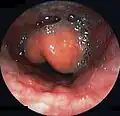

Diagnosis may be confirmed by direct inspection using a laryngoscope, although this may provoke airway spasm.[20] If epiglottitis is suspected, attempts to visualize the epiglottis using a tongue depressor are discouraged for this reason; therefore, diagnosis is made on basis of indirect fiberoptic laryngoscopy carried out in a controlled environment like an operating room.[20] An infected epiglottis appears swollen and is described as having a "cherry-red" appearance.[21] Imaging is rarely useful, and treatment should not be delayed for this test to be carried out.[20]

Swollen epiglottis in laryngoscopy